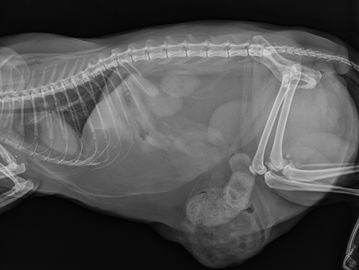

At Grove Small Animal Hospital, we’re proud to offer advanced diagnostic imaging to support the health and wellbeing of your pets.

Our digital radiography (X-ray) system allows us to capture high-quality images quickly and safely—helping us diagnose everything from fractures to internal conditions with clarity and precision.

For more complex cases, we collaborate with board-certified radiologists who can provide expert interpretations to ensure your pet gets the most accurate diagnosis possible.